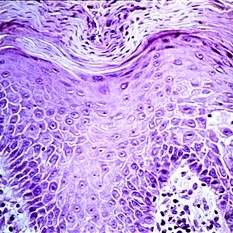

Slide 5-1 Slide 5-1Feb 20 2019 by Lancaster Course in Ophthalmology Normal lid skin from a darkly pigmented individual. Condition/keywords: normal eye

Slide 5-2 Slide 5-2Feb 20 2019 by Lancaster Course in Ophthalmology The thickened epidermis shows acanthosis (prickle cell proliferation) and parakeratosis (retention of nuclei in desquamating surface-layer cells). Condition/keywords: acanthosis, epidermis, Keratosis pilaris (KP), prickle cell proliferation